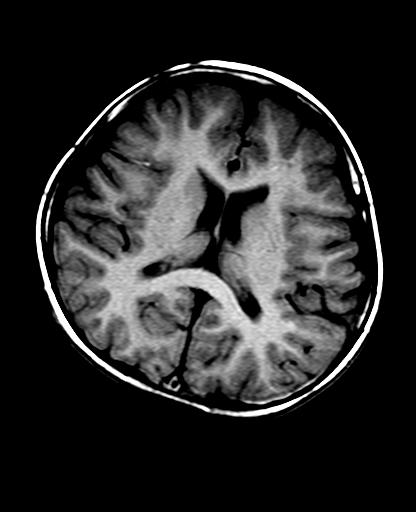

标题: PED2848:脑内病变2

头痛10天、间断呕吐2天。f 6岁

入科化验血清铜及铜兰蛋白均减低,脑脊液正常,血清神经原烯醇化酶明显增高。wbc:5.94x109/l、

临床表现及实验室检查符合肝豆状核变性

符合肝豆状核变性。

mri未见明显异常。但临床支持考虑肝豆状核变性。